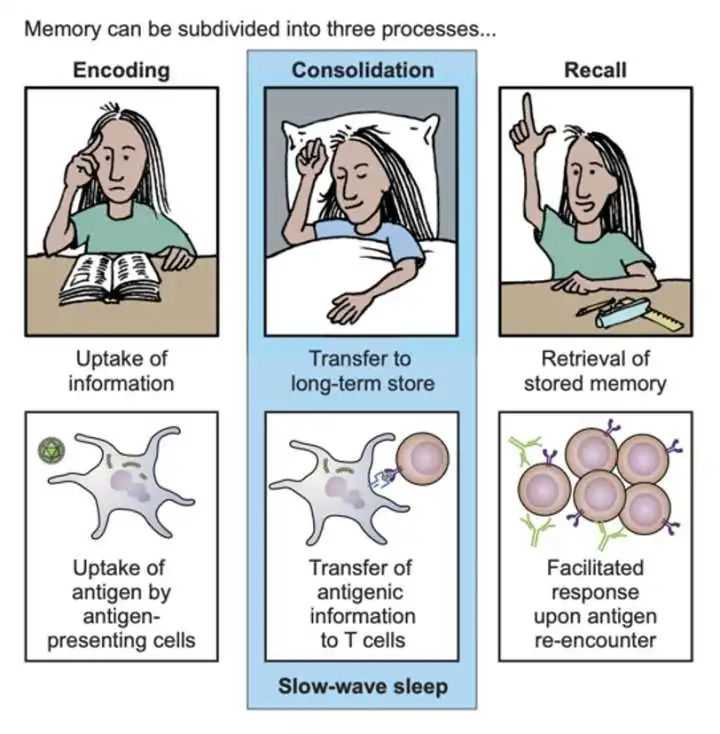

说回熬夜和免疫力。最新的医学研究表明,熬夜可使T细胞及NK细胞的功能显著下降。通过对动物进行睡眠剥夺,发现动物体内一系列免疫指标发生变化,从而证明睡眠不足会增加感染风险。还有一些研究结果表明,睡眠对获得性免疫反应和免疫记忆的形成至关重要。

免疫记忆及获得性免疫均在睡眠中通过免疫细胞之间的通信完成